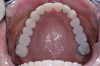

Figure 1  Accurate casts mounted at arbitrary OVD.

Figure 1

Figure 2  The proposed gingival alteration marked on the cast.

Figure 2